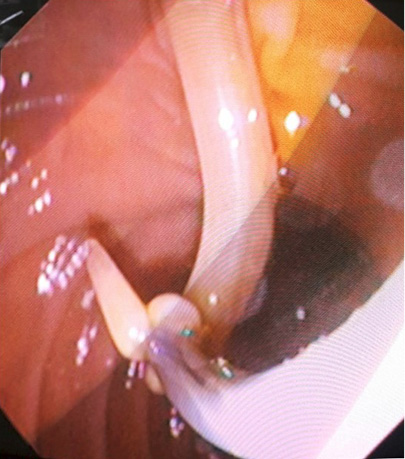

3 pav. Askaridės šalinimas iš BTL, atliekant duodenoskopiją

Pacientei įtarta pilvo skausmų priežastis – tulžies latakų akmenligė, nesant mechaninės geltos. Priimtas sprendimas atlikti duodenoskopiją ir ERC tyrimą. Duodenoskopijos metu įvertinta, kad papilla Vateri yra po PST procedūros. Kontrastavus BTL, pastebėtas >5 cm ilgio 4 mm skersmens prisipildymo defektas lygiais kontūrais. Naudojant Dormia krepšelį, iš tulžies latako pašalintas prisipildymo defektas – askaridė (3–5 pav.). Atlikus procedūrą, pacientės sveikatos būklė pagerėjo, pilvo skausmas regresavo, nesikartojo. Papildomai atlikta dehelmintizacija mebendazolu, antihelmintiniu vaistiniu preparatu („Vermox“).